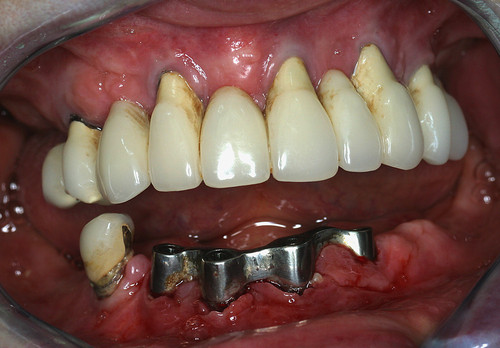

Ce volume osseux obtenu permet facilement la mise en place d’implants en remplacement des molaires absentes et la mise en place d’une prothèse fixe fonctionnelle et esthétique (fig.32)

Fig. 32

Mise en place des implants et prothèse finale